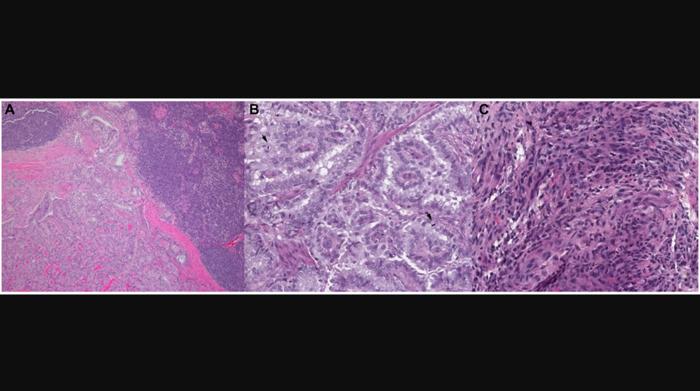

In this new paper, researchers Mark Lee and Luc GT Morris from New York Presbyterian Hospital and Memorial Sloan Kettering Cancer Center discuss thyroid cancer. A subset of thyroid cancers present at advanced stage or with dedifferentiated histology and have limited response to standard therapy. Tumors harboring the BRAF V600E mutation may be treated with BRAF inhibitors; however, tumor response is often short-lived due to multiple compensatory resistance mechanisms.

DNA sequencing and RNA expression profiling show that thyroid tumors that dedifferentiate after BRAF inhibition are enriched in known genetic alterations that mediate resistance to BRAF blockade, and may also drive tumor dedifferentiation, including mutations in the PI3K/AKT/MTOR (PIK3CA, MTOR), MAP/ERK (MET, NF2, NRAS, RASA1), SWI/SNF chromatin remodeling complex (ARID2, PBRM1), and JAK/STAT pathways (JAK1). Given these findings, recent investigations have evaluated the efficacy of dual-target therapies; however, continued lack of long-term tumor control illustrates the complex and multifactorial nature of these compensatory mechanisms. Transition to an immune-suppressed state is another correlate of BRAF inhibitor resistance and tumor dedifferentiation, suggesting a possible role for concurrent targeted therapy with immunotherapy.